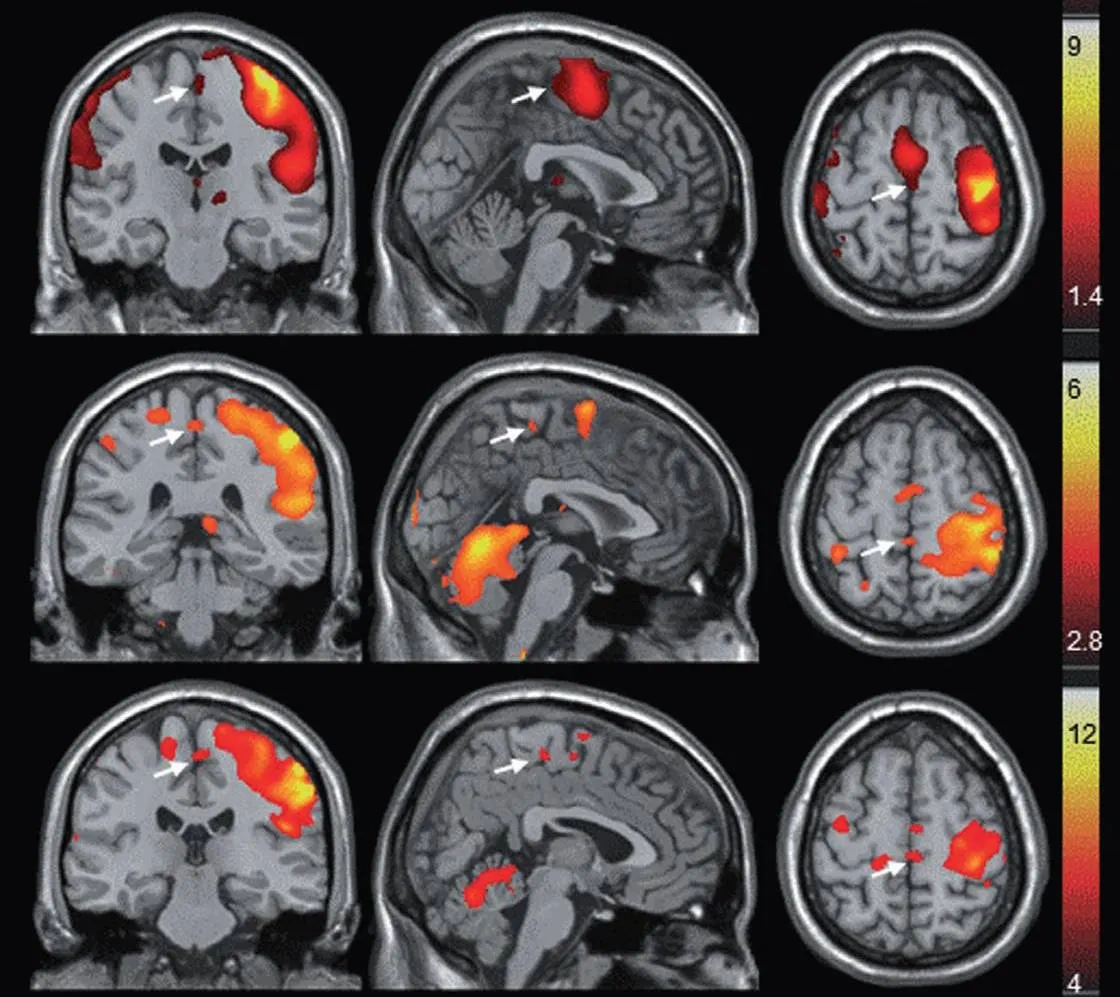

#3: Clears Brain Fog & Restores Mental Sharpness

.png)

Estrogen receptors exist throughout your entire brain—in areas responsible for memory, language, focus, decision-making, and emotional regulation.

When estrogen drops:

● Verbal fluency declines (you can't find words)

● Working memory fails (you forget what you're doing)

● Processing speed slows (everything takes longer)

● Executive function suffers (decisions become exhausting)

Bioidentical estradiol restores all of this.